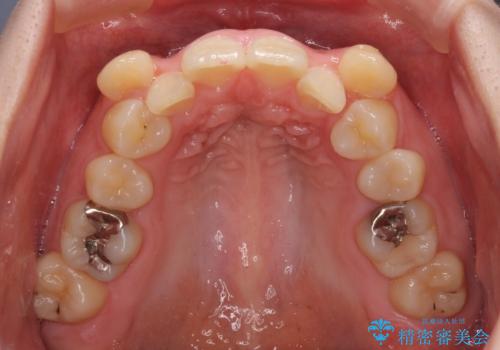

著しい八重歯を短期間で改善 ワイヤー装置による抜歯矯正

- 八重歯と下顎小臼歯の欠損を気にして来院された患者様です。

下顎小臼歯の欠損により過蓋咬合となっていたため、下顎は臼歯を起こすことで咬み合わせを改善し、八重歯は第一小臼歯2本を抜歯し、補助装置を使用して速やかに改善することとしました。

著しい過蓋咬合の改善が必要であった割には、治療期間は2年強と標準的でした。

八重歯は3,4か月で速やかに改善されました。